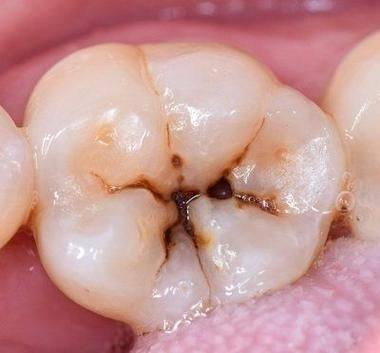

成人由于生活习惯、饮食习惯等因素,也容易出现龋齿。成人龋齿早期症状与其他阶段有所不同。成人的牙齿矿化程度相对较高,但由于长期的口腔使用和磨损,牙齿表面可能会有一些细微的裂纹或磨损。在成人龋齿早期的图片中,我们可以看到这些部位更容易被细菌侵袭,出现龋齿。

成人可能会因为工作繁忙等原因,忽视口腔卫生,导致龋齿的发生。成人龋齿早期可能会出现牙齿表面颜色改变,如出现黑色或褐色的小点。同时,在吃食物时,可能会感觉到牙齿有轻微的不适。通过成人龋齿早期症状图片,我们可以针对性地关注自己的口腔状况。

成年初期,人们的生活方式和饮食习惯可能会发生较大变化,这也会影响口腔健康。成年初期龋齿通常与生活压力、饮食不规律等因素有关。在成年初期龋齿的图片中,我们可以看到牙齿邻面更容易出现龋齿。这是因为邻面清洁相对困难,细菌容易在此滋生。

成年初期的人可能会因为社交活动增多,摄入更多的甜食和饮料,从而增加了龋齿的风险。此时,牙齿可能会出现一些早期的脱矿现象,在图片上表现为牙齿表面的颜色不均匀。及时查看成年初期龋齿的图片,有助于我们在这个阶段预防和治疗龋齿。